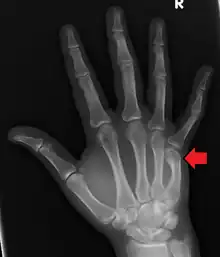

| Boxer's fracture of the 5th metacarpal head from punching a wall | |

A boxer's fracture is the break of the fifth metacarpal bone of the hand near the knuckle.[4] Occasionally, it is used to refer to fractures of the fourth metacarpal as well.[1] Symptoms include pain and a depressed knuckle.[2]

Classically, it occurs after a person hits an object with a closed fist.[3] The knuckle is then bent towards the palm of the hand.[3] Diagnosis is generally suspected based on symptoms and confirmed with X-rays.[3]